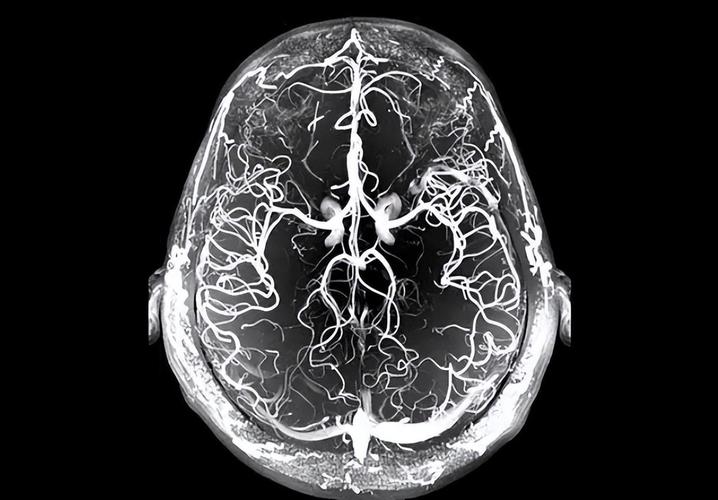

(图片来源网络,侵删)